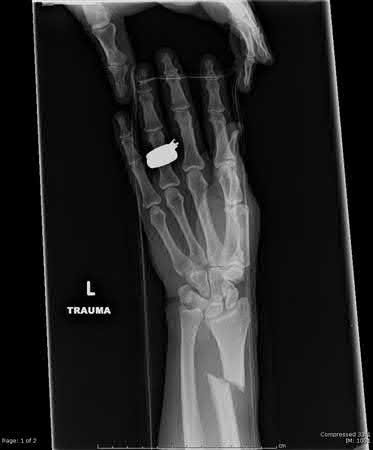

A 25-year-old male sustains an ankle fracture dislocation and undergoes open reduction and internal fixation. He returns to clinic five months following surgery complaining of continued ankle pain and instability with weight bearing. His immediate post-operative AP radiograph is seen in Figure A. Which of the following could have prevented this patient from developing persistent pain?

The patient presents with continued ankle pain and instability following open reduction and internal fixation. The radiograph in figure A demonstrates inadequate restoration of fibular length, likely leading to continued tibiotalar instability.

Illustration A demonstrates fibular malreduction with dislocation of the fibula anterior to the tibial incisura. Illustration B shows a comminuted fibula fracture along with a measurement of length from an intact fibula. The arc from the lateral process of the talus to the peroneal groove of the distal fibula is known as the "dime" sign and should remain unbroken if fibular length has been restored. Illustration C demonstrates the use of a push-pull screw and lamina spreader to regain length intraoperatively for a comminuted fibula fracture.

Chu and Weiner review management of malunions of the distal fibula. The authors state that restoration of fibular length, alignment and rotation leads to reduction of the talus, provides a buttress to talar motion in the setting of an incompetent deltoid, and allows the syndesmotic ligaments to heal at the appropriate tension.

Wikeroy et al conducted a study of patients from a prior prospective, randomized control trial comparing different methods of syndesmotic fixation. There was no significant difference in outcomes between tricortical or quadricortical 3.5mm screw fixation, however worse outcomes were seen with associated posterior malleolar fractures, obesity, a difference in sydesmotic width of 1.5mm or greater, and a CT confirmed tibio-fibular synostosis.

Sinha et al present a simple technique for fibular lengthening in the setting of distal fibula malunion. They found high union rates and improved AOFAS scores at short-term follow up with their technique.